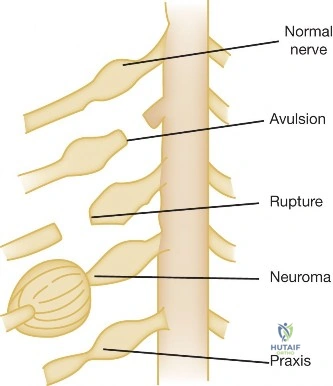

* To visualize the integrity of the brachial plexus roots, trunks, and divisions.

* To differentiate preganglionic (root avulsion from spinal cord) from postganglionic injuries (rupture or neuroma in continuity).

* To identify pseudomeningoceles, which are highly suggestive of root avulsions.

Interpretation: The MRI findings suggested a severe postganglionic injury to the C5 and C6 nerve roots, either a complete rupture or a neuroma-in-continuity, rather than a definitive preganglionic avulsion. This information is crucial for determining the potential for nerve repair (grafting) versus nerve transfer.